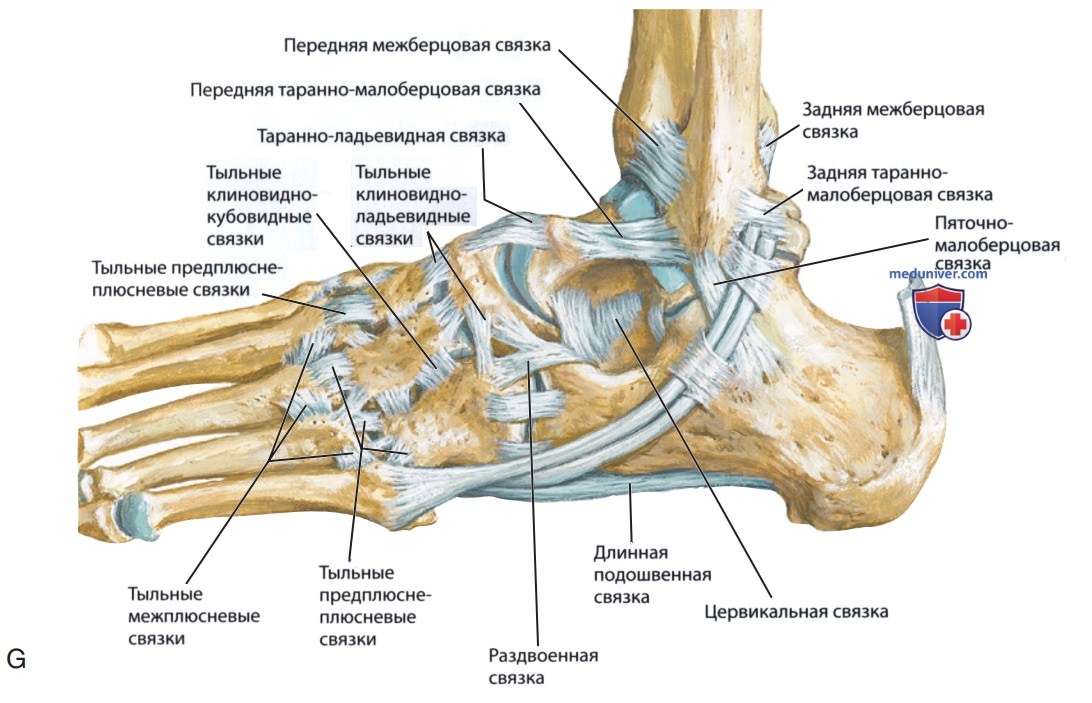

Анатомические фото голеностопного сустава и его суставных поверхностей